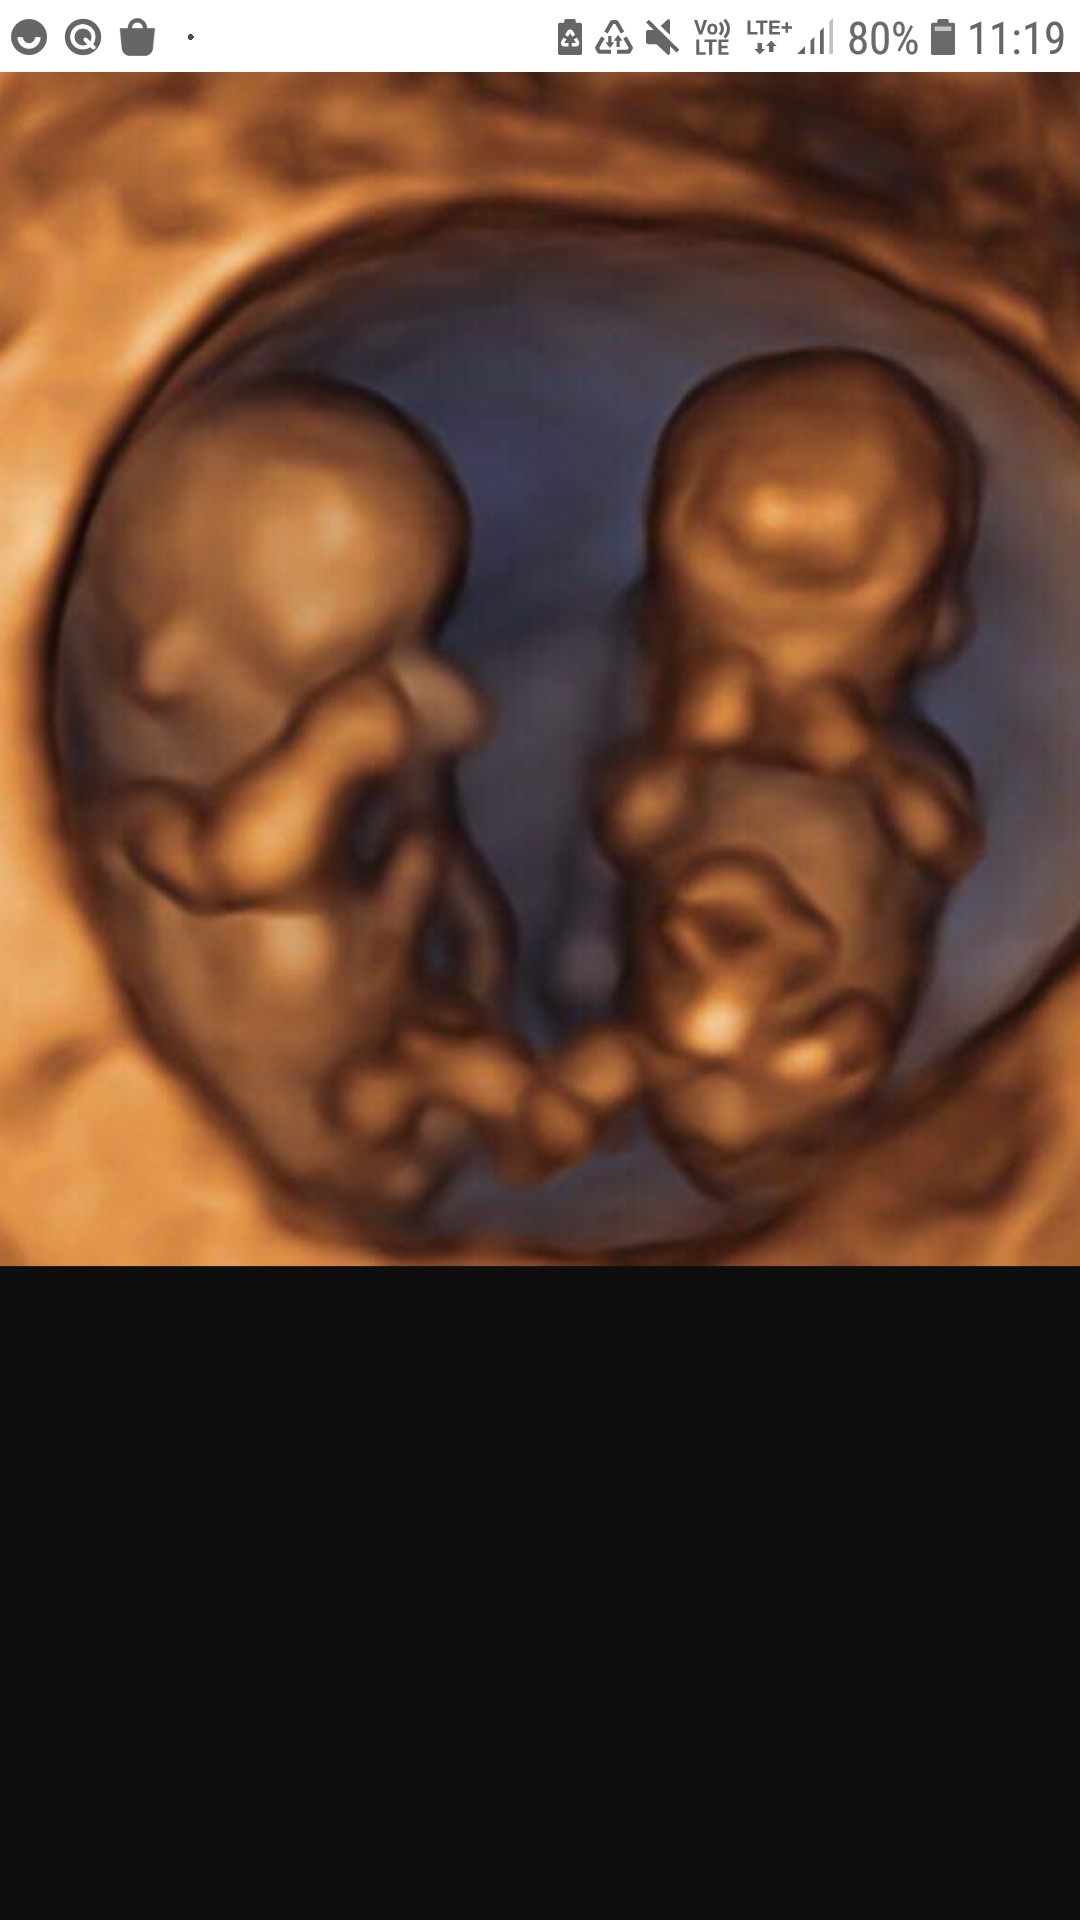

Wow😍 ale ekstra. Niesamowite jest to jak szybko fasolka zmienia się w malutkiego człowieczka 😍

a w ogole Ty bedziesz miala super zdjecia 😍 moj gin fotografowal takie oto blizniaki😀 widac ze to wczesna ciaza jeszcze.

Załączniki

• Screenshot_20201021-111910_Samsung Internet.jpg

Screenshot_20201021-111910_Samsung Internet.jpg

135,1 KB · Wyświetleń: 101